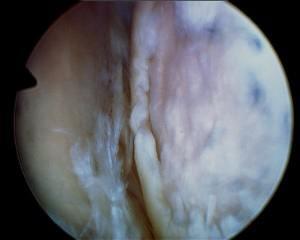

Torn biceps tendon

Labral tear

Yes, definitely, the main one being the ability to visualize and treat other pathological conditions inside the shoulder joint which are known to frequently co-exist with rotator cuff tears, i.e., DJD, loose bodies, labral tears and biceps lesions. With the open approach, even a large tear will allow visualization of only a small portion of the inside of the joint, whereas arthroscopically the entire inside of the joint can be assessed.

One category of problems very frequently associated with rotator cuff tear is biceps lesions, including tendonitis, tearing or instability. Loose bodies or cartilaginous debris are commonly seen with osteoarthritis and labral tears. All of these can be difficult to visualize with plain x-rays and even MRI is

not 100% accurate. Arthroscopy offers the most comprehensive way to thoroughly evaluate the shoulder and thereby increase the likelihood of a successful result that might otherwise be compromised by a missed diagnosis.